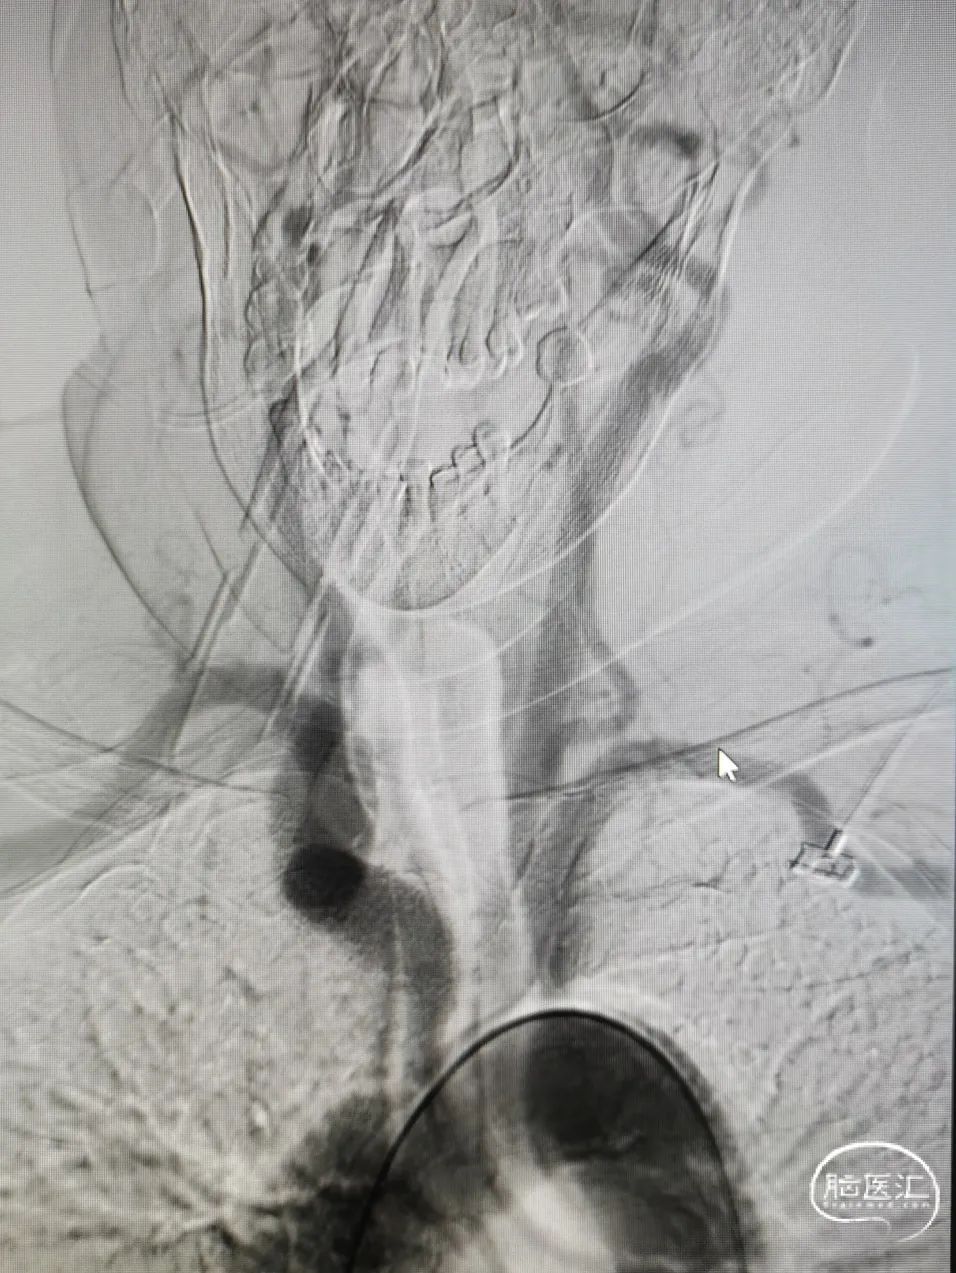

DSA造影

造影提示主动脉弓开口尚可,但颈动脉迂曲明显。

前交通囊状动脉瘤约4mm╳3mm,瘤颈约4mm。

右颈内动脉交通段以远瘤样扩张,载瘤动脉完全瘤化,局部可见多处小阜突起,无明显瘤颈,最大约16mm╳11mm。

右侧后交通动脉自瘤体远端发出。

右侧大脑中动脉直径约3mm,颈内动脉海绵窦段约4.5mm。

图4